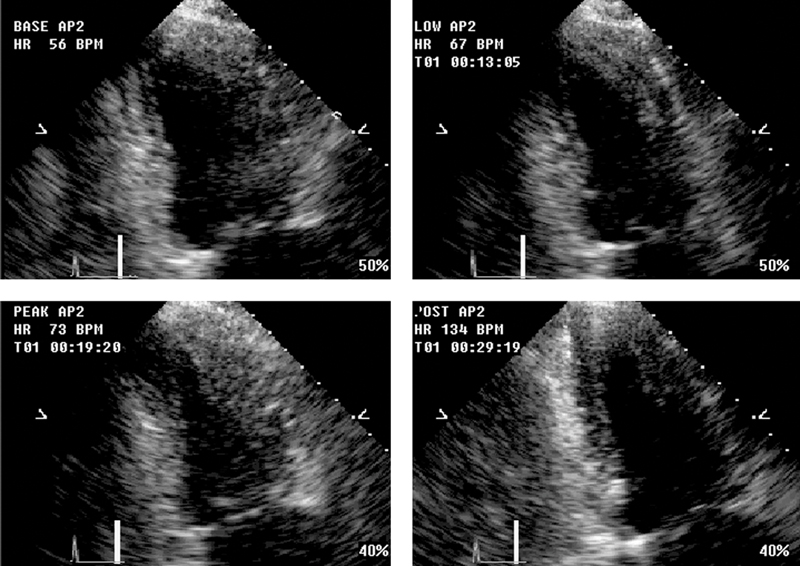

فحوصات تشخيصية لبعض امراض القلب والشرايين التاجية